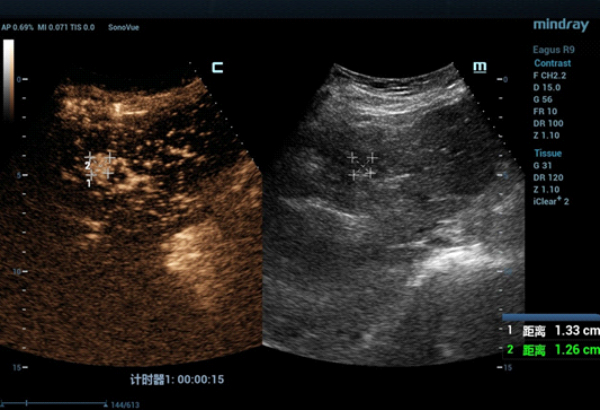

W konwencjonalnym obrazowaniu USG w skali szaro?ci nie uda?o si? uwidoczni? guza w segmencie IV zaobserwowanego w badaniu TK jamy brzusznej. W badaniu USG z kontrastem (contrast-enhanced ultrasound, CEUS) zmiana wykazywa?a wzmo?one unaczynienie w fazie t?tniczej (Obraz 2.) z izointensywnym wzmocnieniem w fazach wrotnej i pó?nej (Obraz 3.)./p>

U pacjentki zaplanowano zabieg ablacji mikrofalowej (microwave ablation, MWA) pod kontrol? USG, jednak z uwagi na fakt, ?e nie uda?o si? uwidoczni? zmiany w konwencjonalnym badaniu USG, w celu zapewnienia dok?adnego pozycjonowania elektrody mikrofalowej wykorzystano obrazowanie metod? fuzji obraz√≥w: ultrasonograficznego i TK z kontrastem (Nagranie 1, Obraz 4вАУ7).

Guz by? izoechogeniczny i nie mo?na by?o wyra?nie uwidoczni? go w badaniu USG 2D w skali szaro?ci, zatem konwencjonalna kontrola wy??cznie z zastosowaniem USG mog?a skutkowa? niedok?adnym pozycjonowaniem i niepe?n? ablacj?. Z kolei obrazowanie z wykorzystaniem fuzji obrazów uzyskanych w badaniu USG w czasie rzeczywistym z danymi uzyskanymi w badaniu TK z kontrastem umo?liwi?o dok?adne pozycjonowanie elektrody i skuteczne leczenie zmiany metod? przezskórnej MWA. Przed zabiegiem przeprowadzono badania CEUS w celu potwierdzenia umiejscowienia guza oraz po zabiegu w celu oceny obszaru poddanego ablacji i potwierdzenia skuteczno?ci leczenia.